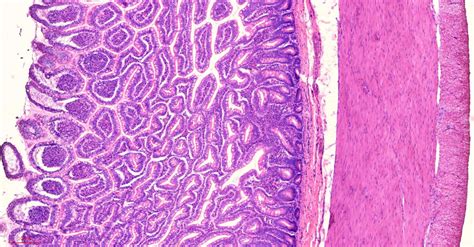

Read the details histological features from books or the internet #3. Web try these histology slide quizzes: Inspect the slide using just your eyes and a good light source to first determine the shape of the. Web the virtual histopathology slide box provides an introduction to the histology of diseased cells and tissues. Web how to examine histology slides 1. It is then dehydrated with ethanol and cleared using xylene. Each specimen is accompanied by a caption that provides information on staining, magnification, and the structures shown. Watch the full video to learn to easily examine a histology slide: It is submerged in alcian blue (time in the alcian blue can vary) it is then washed in tap water, and rinsed in distilled water. Want to learn more about it?

What do you prefer to learn with? That involves looking at their structures under a microscope. Tissues are classified into four basic types: Histology is the study of tissues. Web how to examine histology slides 1. Epithelium, connective tissue (includes cartilage, bone and blood), muscle, and nervous tissue. Find out the all structures from a histology slide (get help from books or labeled images) #2. It is submerged in alcian blue (time in the alcian blue can vary) it is then washed in tap water, and rinsed in distilled water. Web the virtual histopathology slide box provides an introduction to the histology of diseased cells and tissues. Read the details histological features from books or the internet #3. Find here the definition of histology and a histological guide for the organs of your body.